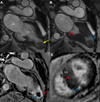

Case report: We present a case of HCM with midventricular hypertrophy and obstruction diagnosed after a CT scan of the abdomen incidentally revealed a filling defect in the left ventricular apex. Transthoracic echocardiography demonstrated mid left ventricular hypertrophy and obstruction, as well as an aneurysmal apex containing a large thrombus. Cardiovascular MRI showed a spade-shaped left ventricle with midcavitary obliteration, an infarcted apex and regions of myocardial fibrosis. Due to the risk of embolization and a relative contraindication to anticoagulation, the patient underwent surgery including thrombectomy, septal myectomy and aneurysmal ligation.

Conclusions: Hypertrophic cardiomyopathy with midventricular hypertrophy leads to cavity obstruction, increased apical wall tension, ischemia and ultimately fibrosis. Over time, patchy apical fibrosis can develop into a confluent scar resembling a transmural myocardial infarction in the left anterior descending coronary artery distribution. Aneurysmal remodeling of the left ventricular apex potentiates thrombus formation and risk of cardioembolism. For these reasons, hypertrophic cardiomyopathy with midventricular obstruction portends a particularly poor prognosis and should be recognized early in the disease process.